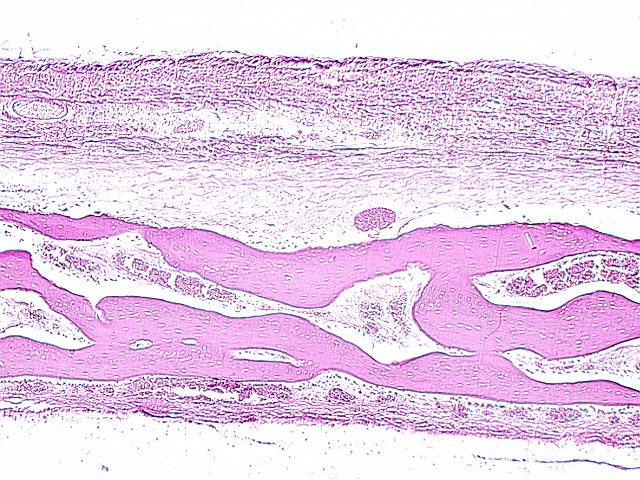

INTRAMEMBRANOUS BONE DEVELOPMENT

![]() Flat bones, like the skull or jaw bone develop from clusters of condensed mesenchyme. A developing fetal skull is shown in the above photo. Areas of condensed mesenchyme lie around the shelves and spicules of bone. Look for these areas in your slide 23. The following photos show spicules of developing bone from this slide. Find osteoblasts, osteocytes, and condensed mesenchyme. Also, can you find osteoclasts?